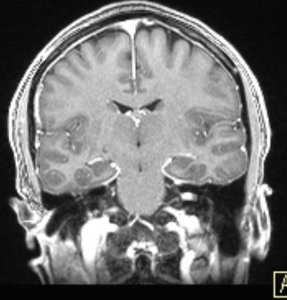

Ενδοκαναλικό Ακουστικό Νευρίνωμα αριστερά